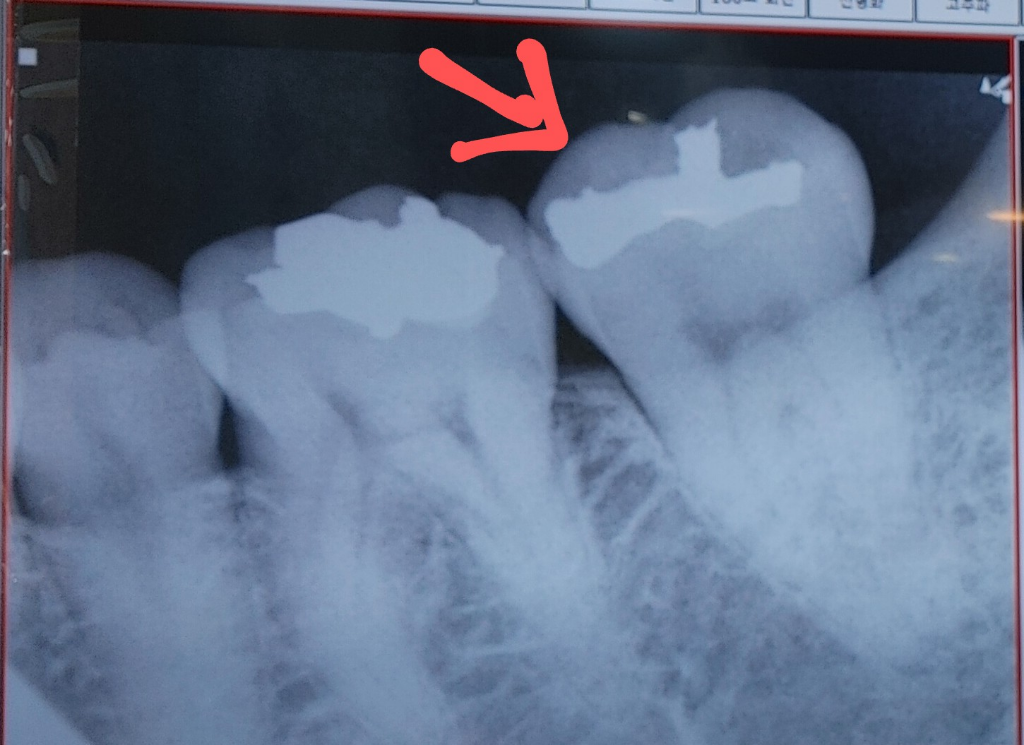

치과 어금니 시림 통증 신경치료

저번주 목요일이 어금니이 찬물 마시면 시림과 통증 있는데. 씹거나 더운물 가글은 괜찮습니다.

10년전에 인레이치료 하였고, 작년 11월에 스켈링 하였습니다.

이빨 잇몸 사이 메꾸면 될줄 알았는데, 치과에서 충격으로 신경 뿌리에 염증 있는거 같으니 신경치료 해야 한다고 하는데.

찬물마실때 시림 통증말고 없는데 신경치료를 해야 할까요.

사진으로만 봤을 경우에는 큰 충치가 보이진 않습니다. 하지만 치아의 금이 같다거나 과도한 힘이 가해졌다면 치아가 실을 수 있기 때문에 치아에 가해지는 힘을 줄여보는 것이 좋습니다. 치아의 금이 갔다면 신경치료 후 크라운 치료가 필요할 수 있습니다. 자세한 확인을 위해서 치과에서 진료를 받아보는 것을 권유드립니다

사진이 희미하여 명확하진 않지만 염증의 소견이 보이기도 합니다. 치과 진료 받으신대로 하시면 될 것 같습니다.

위 x-ray사진상 또는 증상을 봐서는 완전한 신경치료의 적응증이라고 할 수는 없는 상태같습니다.

보통은 뜨거운 것에 민감한 반응을 보일때, 자발통이 있을때, 자극원을 제거하고도 민감한 반응이 1분이상 지속될 때 등에 대해서 신경치료를 시행합니다.

다만, 해당 치과의사가 명확히 진단을 내렸고, 뿌리끝 염증을 발견되었다면 신경치료는 불가피합니다.